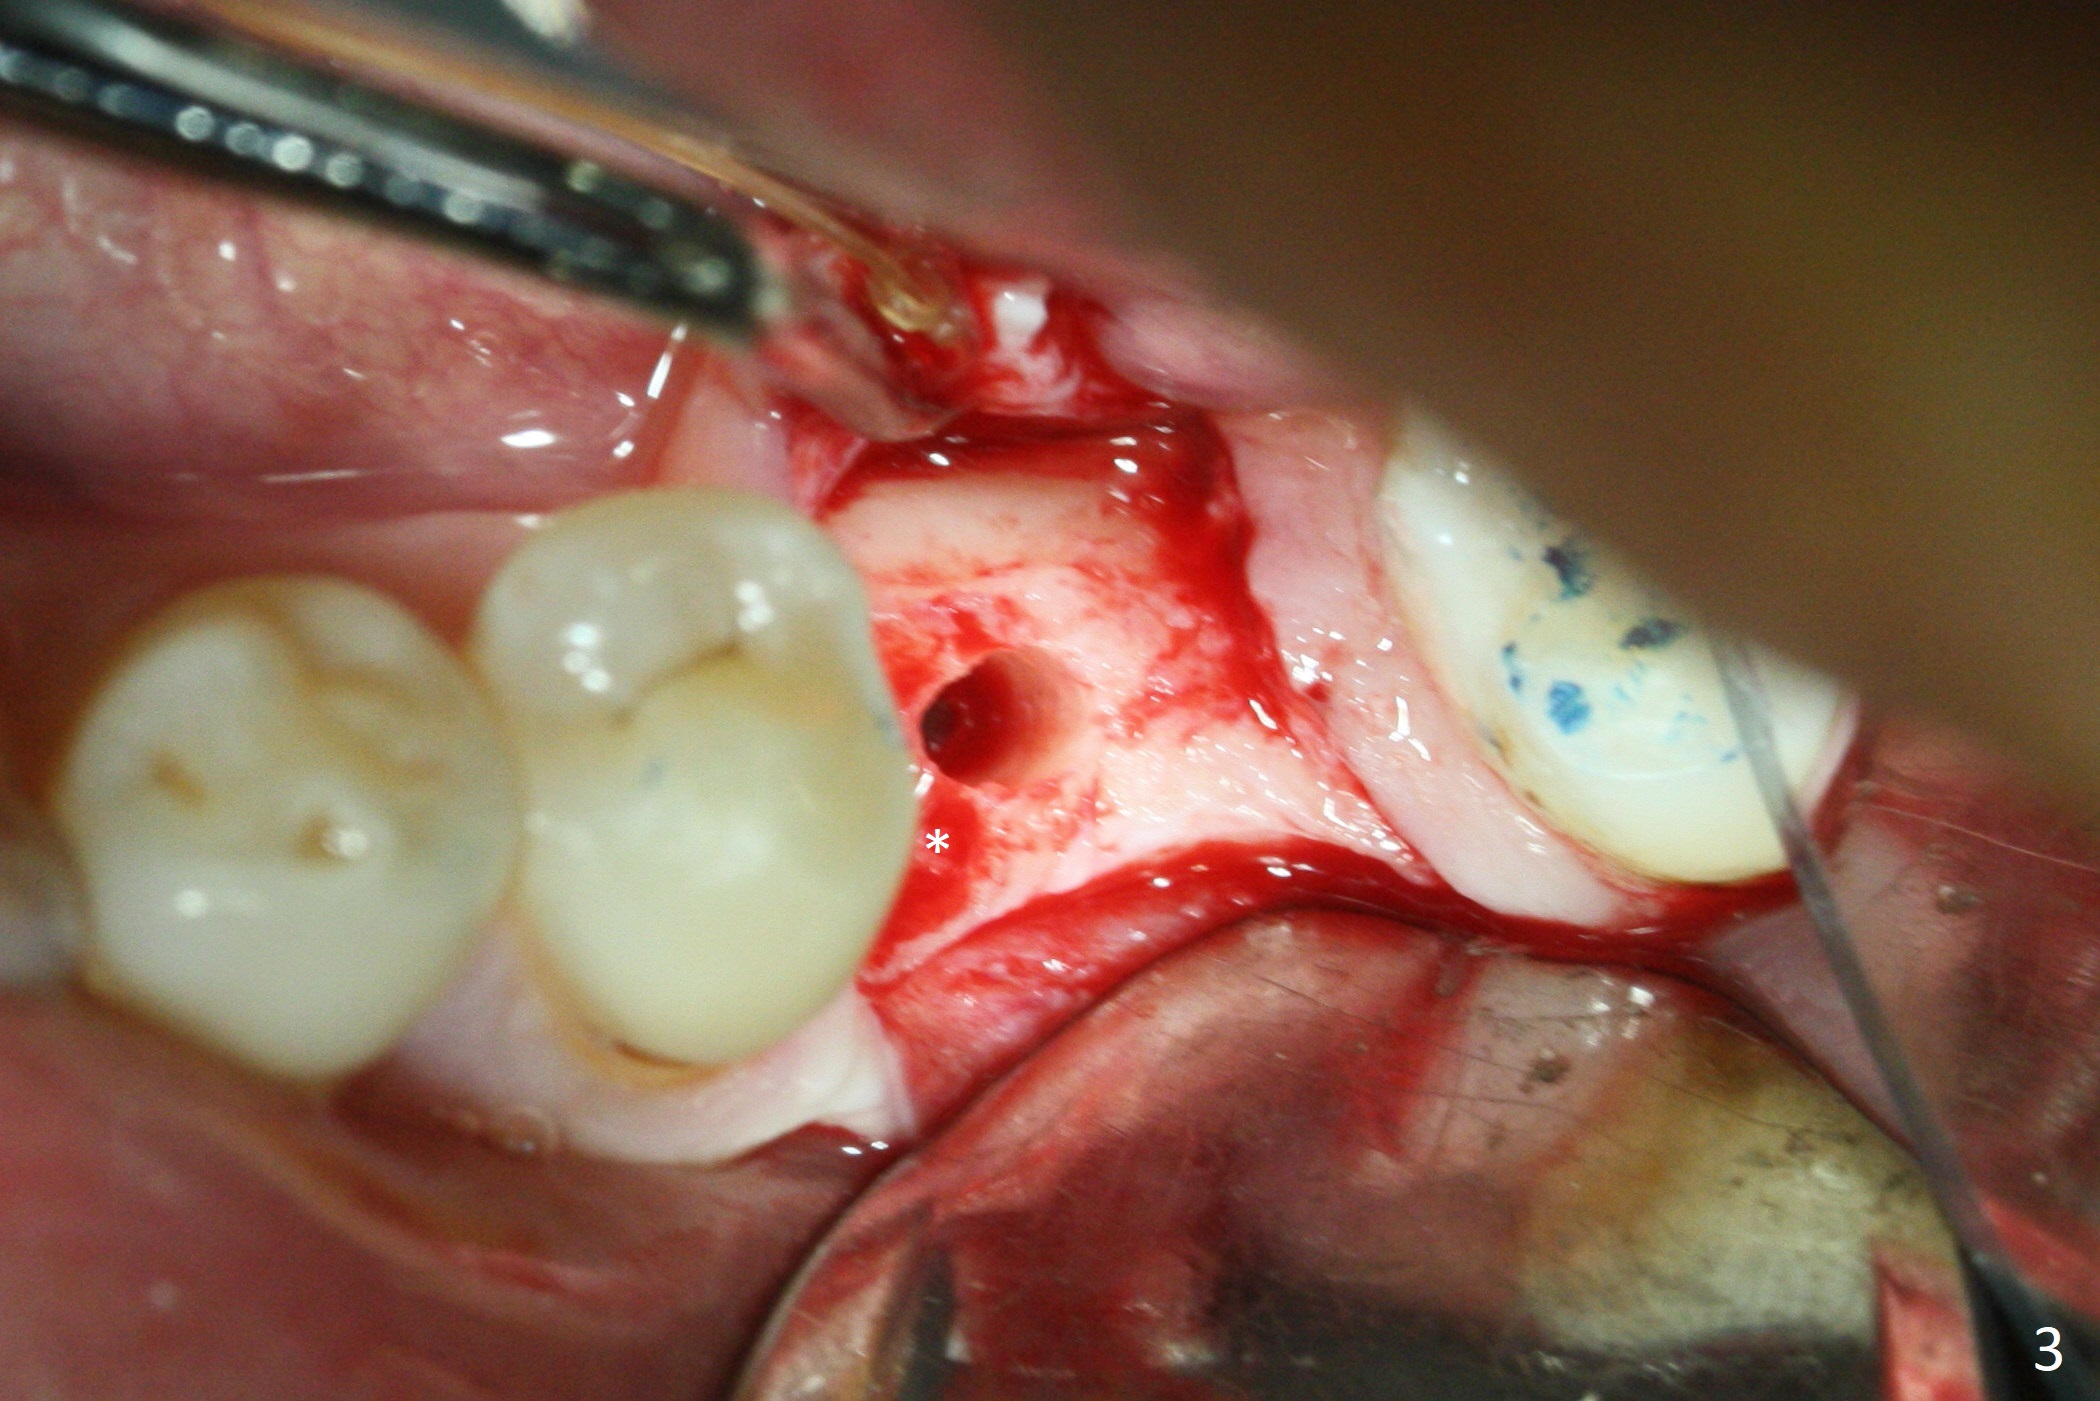

While the mesial ridge is relatively wide associated with residual root at #19 (Fig.1 <), the distal one is narrow (*). Osteotomy is initiated distal to the mesial socket (Fig.2,3 *). Due to the narrow ridge, a 4.5x11 mm implant is placed (Fig.4); before as well as after placement of a 6x4(3) mm abutment, the mesial socket (*) is filled with Vera graft and autogenous bone as well as collagen plug. Following suturing, periodontal dressing is applied to the wound. There is no apparent bone loss 7 months postop (Fig.5,6) or 14 months post cementation (Fig.7). In fact the abutment has been incompletely seated (Fig.5-8), which may be related to #13 failure. The ridge appears to be narrow for the 4.5 mm implant 1.5 years post cementation (Fig.9). When a lady looks skinny with sign of the narrow ridge, choose an implant as narrow as possible.